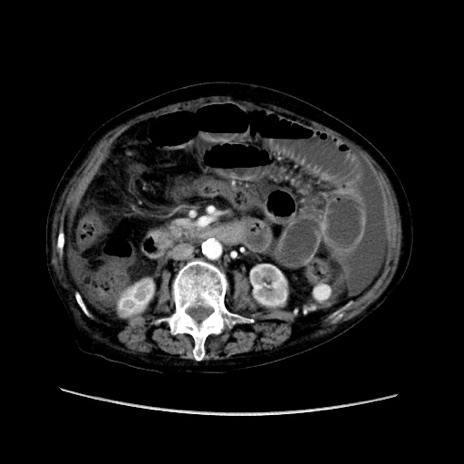

症例31(横断像)

【症例】80歳代 女性

【主訴】腹部膨満感

【現病歴】他院にて肝硬変にてフォロー中。1週間前から便秘、腹部膨満感、臍部腫瘤あり受診となる。

【既往歴】肝硬変

【身体所見】腹部膨隆あり、皮膚変化なし、疼痛なし。

【データ】WBC 4600、CRP 0.25